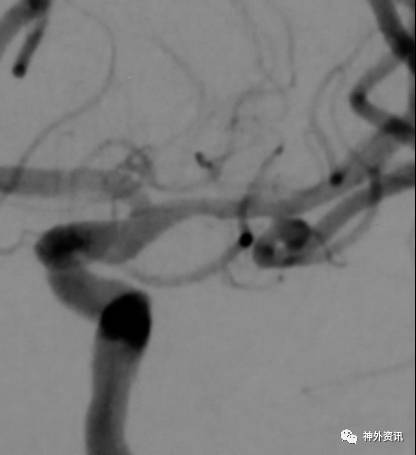

病例一

病例二

病例三

病例四